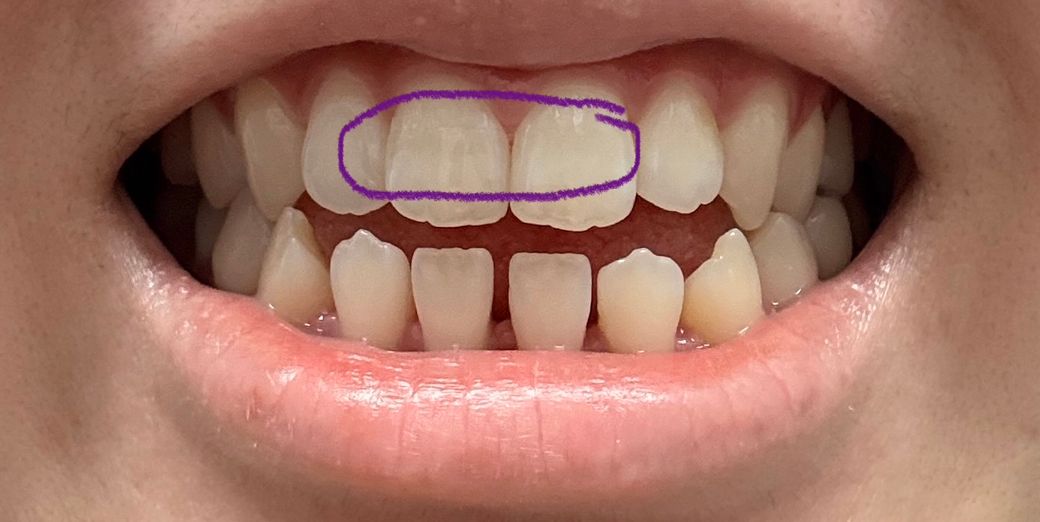

우연히 양치를 하나 봤는데 위 앞니양쪽 에 가로 금이 있더라구요 ㅠㅠ 특히 오른쪽이 좀더 진하구요(사진상은 반대에요) 그냥 외관상 봤을때는 첫번째 사진 파란 네모안에 처럼 좀 금이 살짝 보이는정도고 각도에 따라서 두번째 사진에 보라색 네모친 부분처럼 그림자처럼 보이기도해요 근데 확실히 플래쉬를 비추면 세번째 사진 초록색 네모부분안에 금이 훨씬 잘보여요 ㅠㅠ 혹시나해서 안쪽도 보니 금이 살짝있는데 바깥 금이랑은 같은 위치인지는 모르겠는데 네번째 사진상으로 안나와서 대충 그려서 올립니다! 검은 색 선처럼 약간 가로금이있어요 그런데 제가 원래부터 앞니에 세로로 된 실금은 좀 있었는데 가로로 된 실금은 처음봤어요 ㅠㅠ 그동안 앞니에 큰 충격은 따로 없었고 있어봤자 양치하다 칫솔에 앞니 부딪히는정도가 끝이었어요 몇주전 한번 금있는 치아가 갑자기 시리거나 물 닿았을때 시린건 한번씩 있었는데 그 뒤로는 불편한 건 없었고 금이 만져지거나 하지도않아요 그리고 무엇보다 이번년도 4월에 정기검진했는데 엑스레이도 촬영했는데 이때도 치아 금은 보이지않는다 그러셨거든요 ㅠㅠ 혹시몰라 마지막사진 첨부합니다 이때 금이 있었는지는 모르겠으나 이상없다하셨는데 외상이 없는데 갑자기 금이 생길수 있나요…? 제가 근데 개방교합이라 윗니들이 간격이 좁아서 살짝 튀어나오고 뒤틀어진건 있습니다 ㅠㅠ 일단 사진 보시기에 치료가 필요한 수준인가요..?😭 임플란트 해야할까봐 무서워요 ㅠㅠ 꼭 답변 부탁드릴게요..

• 2번 째 사진